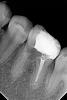

Kolchanov Опубликовано 10 апреля, 2013 Автор Поделиться Опубликовано 10 апреля, 2013 Вот такая вот фигня с этим зубом получилась. Надо оно было ему, нет, теперь уже все равно.С гидороокисью в дистальном она походила с месяцок+ сегодня удалось таки залезть в мезиально-язычный. Мезиально-щечный долбил пока видел, а потом плюнул. Там и так фуркация слезами плачет, судя по снимку.Передал отправил к ортопедам. Чую штамп будет там... Ссылка на комментарий